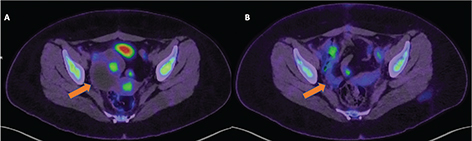

Restaging

The most significant and independent prognostic factor of OS in ovarian cancer patients is the absence or residual disease after primary surgery (28). A positive restaging PET/CT was found to be associated with poor prognosis, and peritoneal spread demonstrated by PET/CT was a significant independent predictor of poor prognosis (33). Moreover, a negative PET/CT has a high negative predictive value (NPV) for the presence of disease and is associated with a very good disease-specific survival rate (Figures 2 and 3).

Fig 2

Figure 2. Restaging. FDG PET/CT images obtained from a 19-yr-old patient with atypical serous ovarian carcinoma referred for restaging following a unilateral oophorectomy and a cystectomy. Image A demonstrates a right-sided malignant ovarian tumor with focal areas of increased FDG accumulation on pre-treatment FDG PET/CT, which demonstrates significant post-treatment improvement in Image B.

Fig 3

Figure 3. Restaging. 18F-FDG PET/CT images obtained from a 69-yr-old patient with Stage IIIC ovarian carcinoma, post debulking surgery and completion of 3rd line chemotherapy, referred for restaging (in the absence of baseline imaging). Arrows indicate the metabolically active primary ovarian tumor in the right adnexa and a right-sided metastatic iliac lymph node.